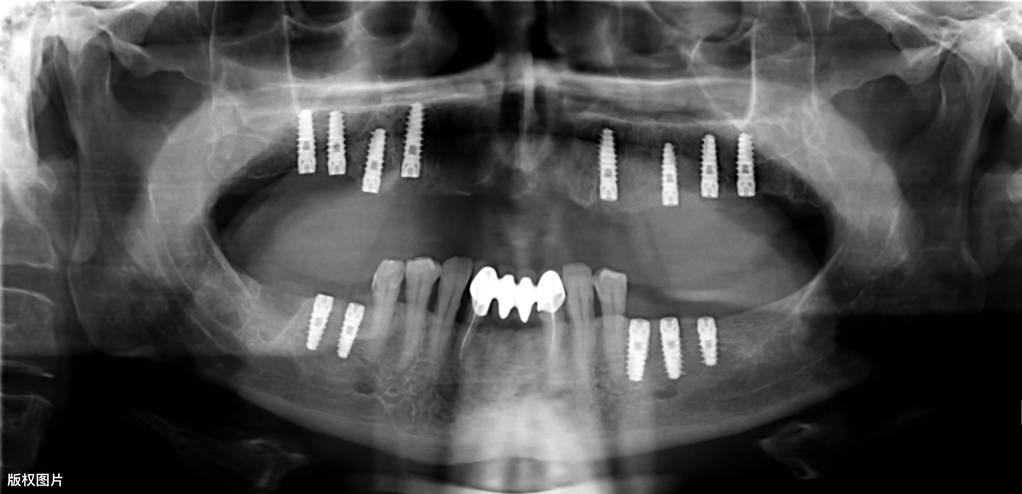

種植牙的一般流程● 術(shù)前檢查:術(shù)前需要拍攝X線片、頜骨CT等,對缺失牙的部位及整個口腔狀況進行系統(tǒng)性檢查。符合種植的適應(yīng)癥,排除禁忌癥后,根據(jù)患者的具體情況制定種植調(diào)節(jié)方案,預(yù)約種植手術(shù)時間。

● 垂直方向的骨吸收不超過種植手術(shù)完成時植入在骨內(nèi)部分長度的1/3(采用標準投照方法X光片顯示)。醫(yī)學(xué)教育|網(wǎng)搜集橫行骨吸收不超過1/3, 種植體不松動。

● 放射學(xué)檢查,種植體周圍骨界面無透影區(qū)。